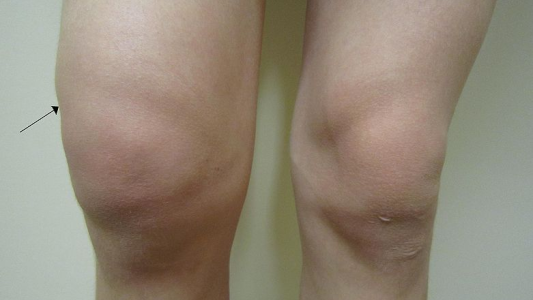

Consiguen identificar la progresión de la artrosis con un análisis de sangre